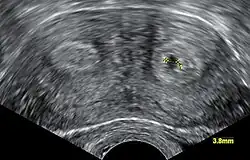

Uterus bicornis mit Frühschwangerschaft in der Sonografie

Es besteht für schwangere Frauen ein höheres Risiko für Frühgeburt und Fehlgeburt, auch für Uterusrupturen.

Die medizinische Diagnose wird in der Regel durch Sonografie gestellt.